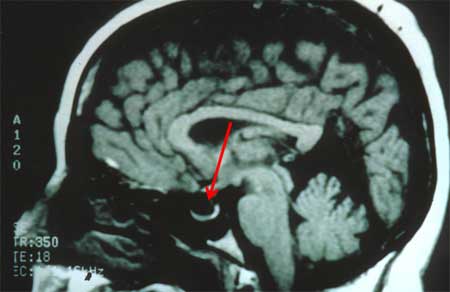

Hipertensão intracraniana idiopática

Ressonância nuclear magnética (RNM) da sela vazia em incidência sagital

Do acervo pessoal do Dr. M. Wall; usado com permissão